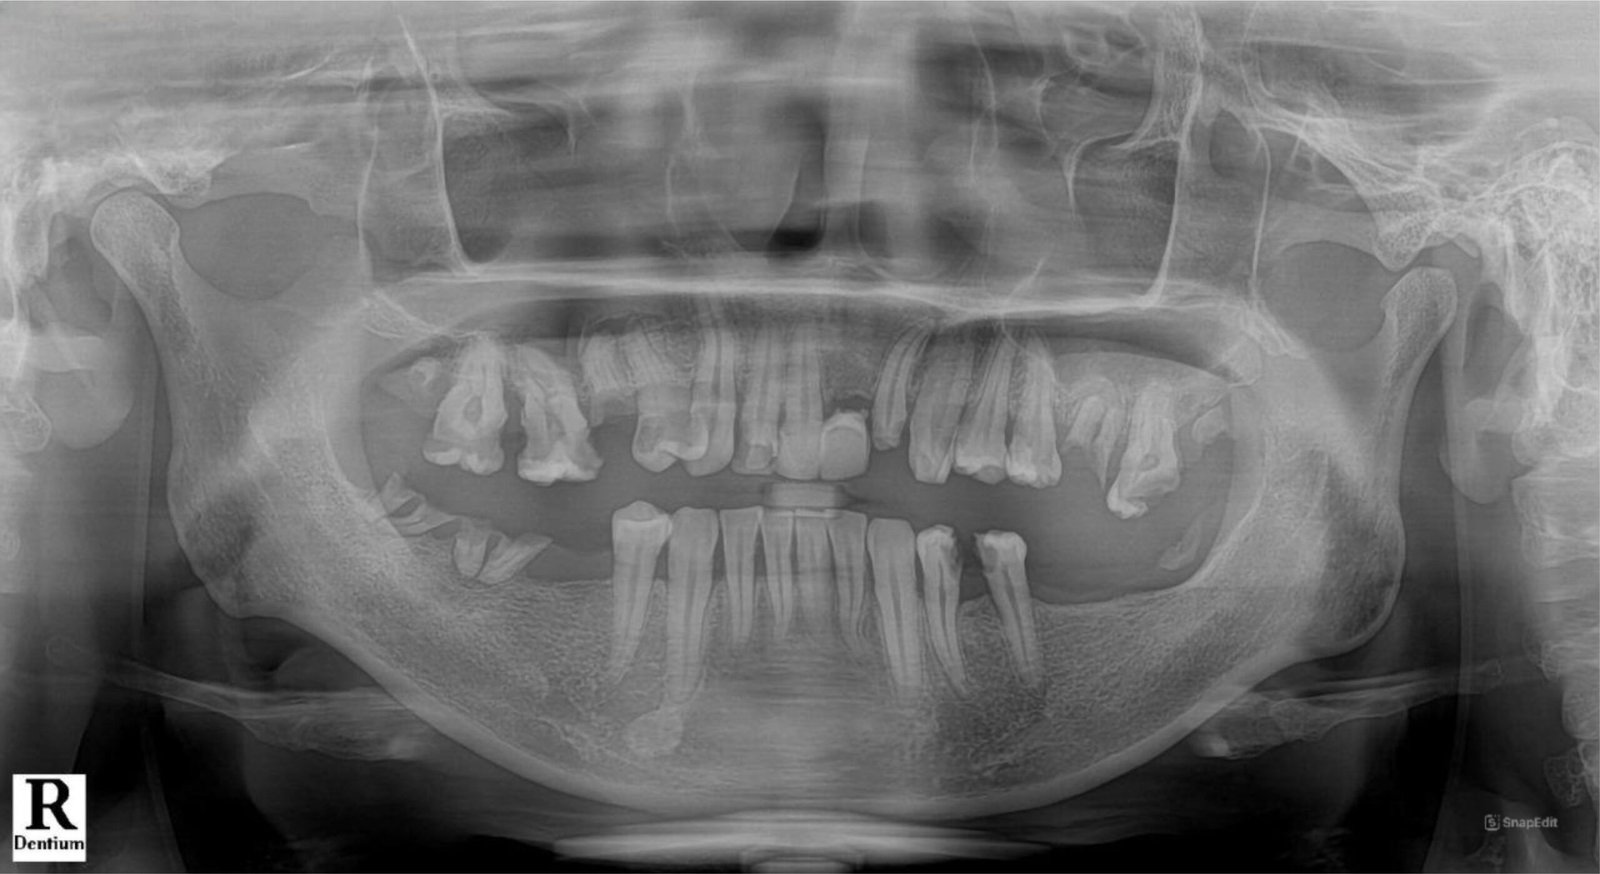

Rontgen Panoramic (OPG) Intra Oral dapat menghasilkan gambar dari seluruh bagian gigi, bahkan tidak cuma gigi, tapi juga gambaran sendi rahang.

Rontgen Panoramic (OPG) Intra Oral dapat menghasilkan gambar dari seluruh bagian gigi, bahkan tidak cuma gigi, tapi juga gambaran sendi rahang.